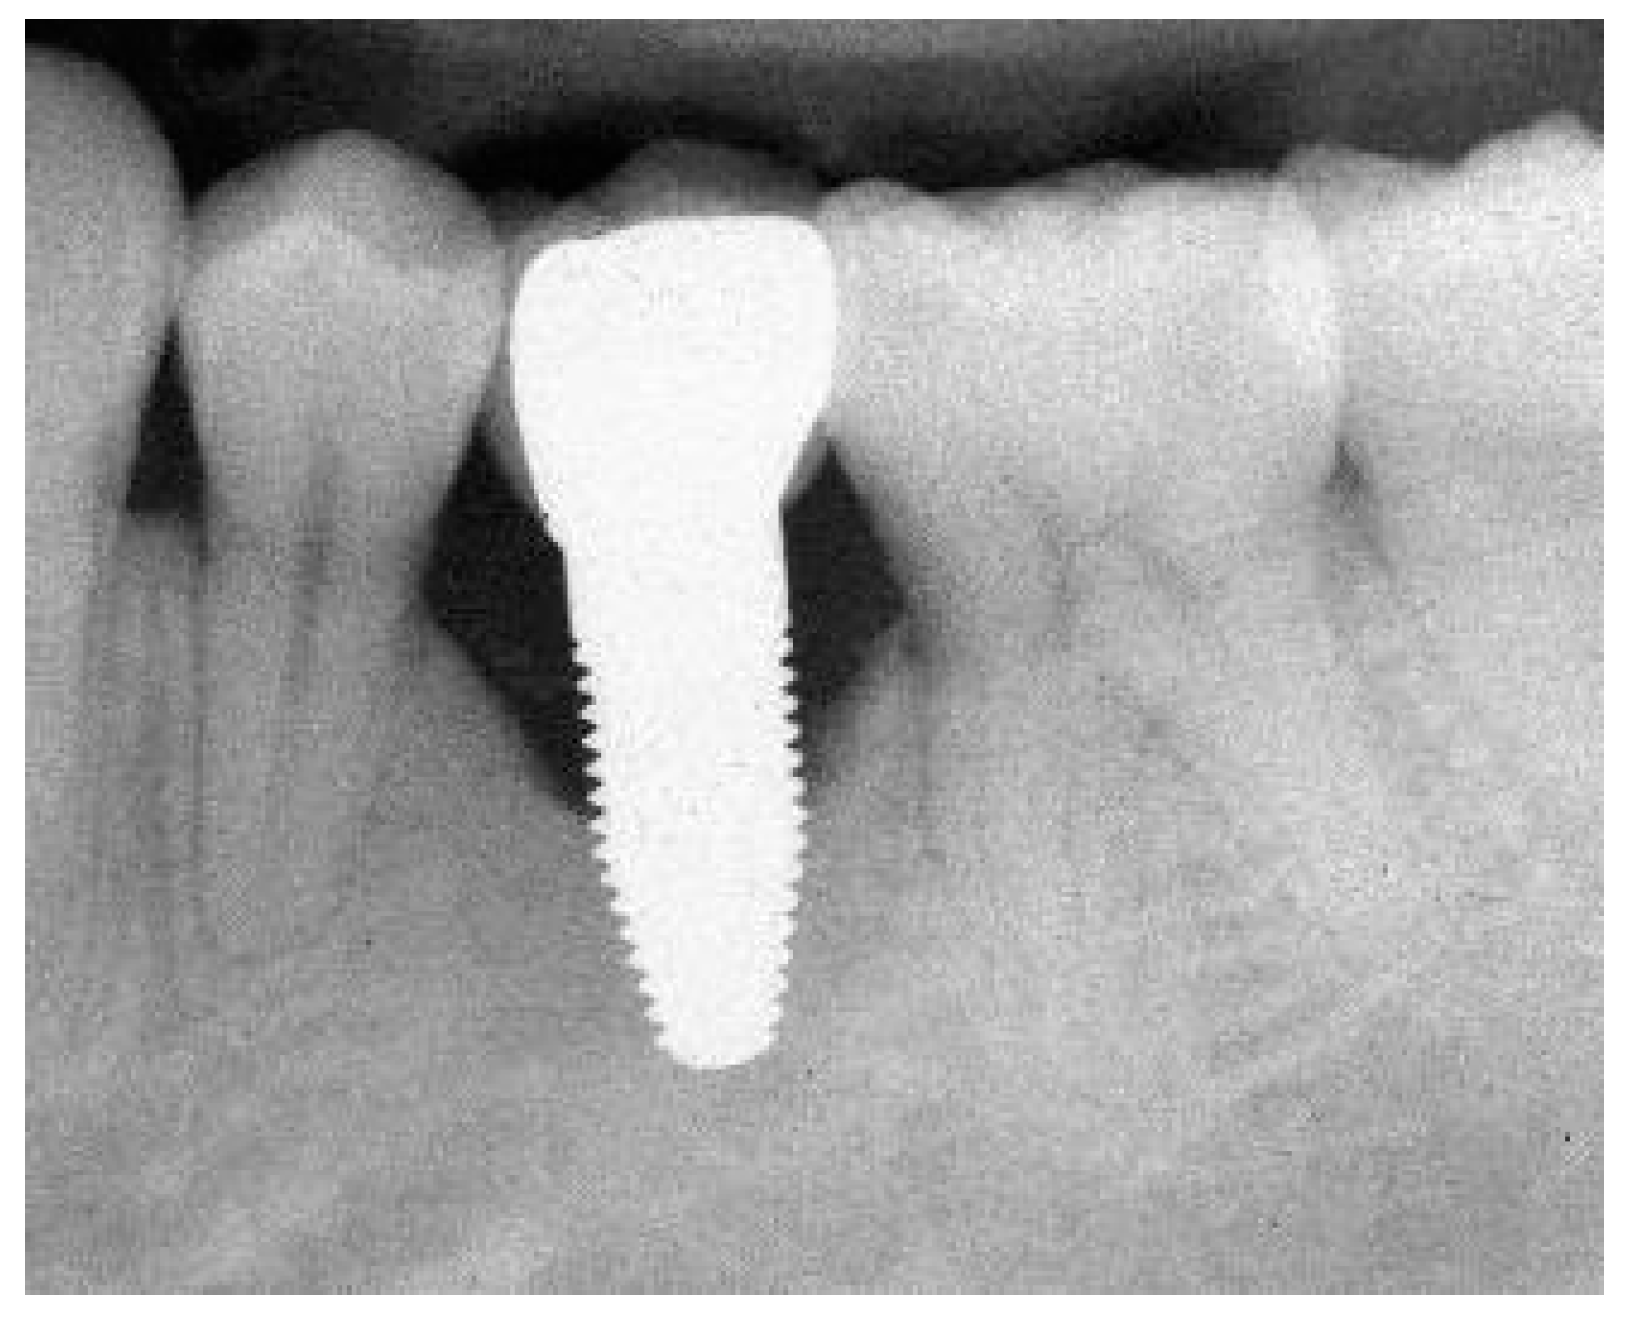

Appendix A. Exemplary Photographs and Radiographs from a Patient at Different Examination Time Points and a Positive Outcome